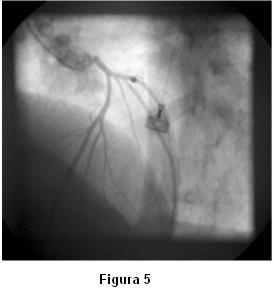

Con el planteo de síndrome coronario agudo de alto riesgo se solicita cineangiocoronariografía que muestra arterias coronarias sin lesiones significativas. Durante el estudio, al momento de cateterizar la coronaria izquierda, se observa severo vasoespasmo de las arterias descendente anterior, circunfleja y sus ramos secundarios (figura 4) con reproducción de los síntomas, que revierte espontáneamente en la siguiente inyección (figura 5).

Antes de la finalización del estudio de la coronaria izquierda reitera espasmo (figura 6) que mejora sin necesidad de administración de vasodilatadores (figuras 7 y 8).